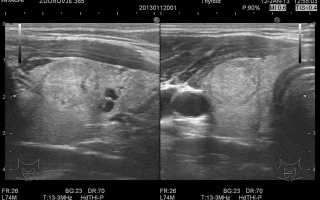

Иллюстрации и схемы по остеопорозу и паращитовидной железе

Раздел: Картинки жизни